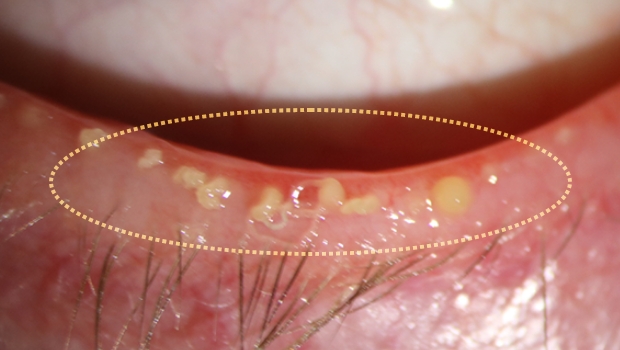

• 시술 후 시술 후

시술 후